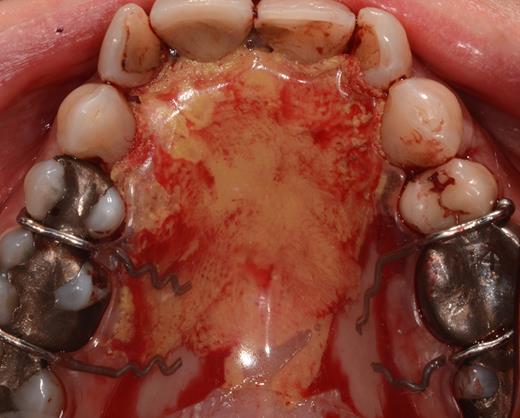

After a sulcular incision on the palatal side from teeth 15 to 25 and an incision in the midline of the palate omitting the incisive papilla and the two orifices of the NPD, two full-thickness mucoperiosteal flaps were raised. Thereafter, the incisive papilla and the whole contents of the incisive canal were enucleated (Figs 4–6). The bony incisive canal was filled with autologous bone harvested from the palatal region (bone scraper) (Fig. 7). A tension-free primary wound closure was achieved by moving the palatal flaps to the midline using single button and interdental vertical mattress sutures (Monocryl 4-0, Ethicon, Johnson & Johnson, USA) (Fig. 8). To avoid wound dehiscence and hematoma, an iodoforme gauze and a palatal plate were applied (Fig. 9). The patient was instructed to rinse three times a day with 0.1% chlorhexidine (formula hospitalis) for 2 weeks postoperatively. Sutures were removed after 14 days.

Preparation of the soft tissue of the incisive canal and the incisive papilla.

Situation after removal of the entire soft tissue contents of the incisive canal.